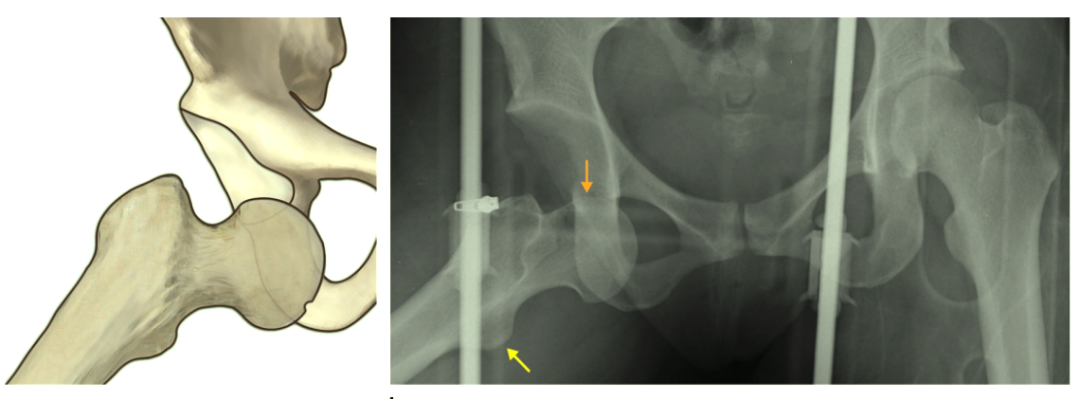

前脱位影像学:

股骨头较健侧大,正位 股骨头下移于髋臼内侧或下方。

![]()

股骨头(橙色箭头)通常位于髋臼内侧下端,髋关节明显外旋,屈曲和外展较轻。髋关节前上脱位相比之下是罕见的,股骨外旋导致小转子明显增加(黄色箭头)。